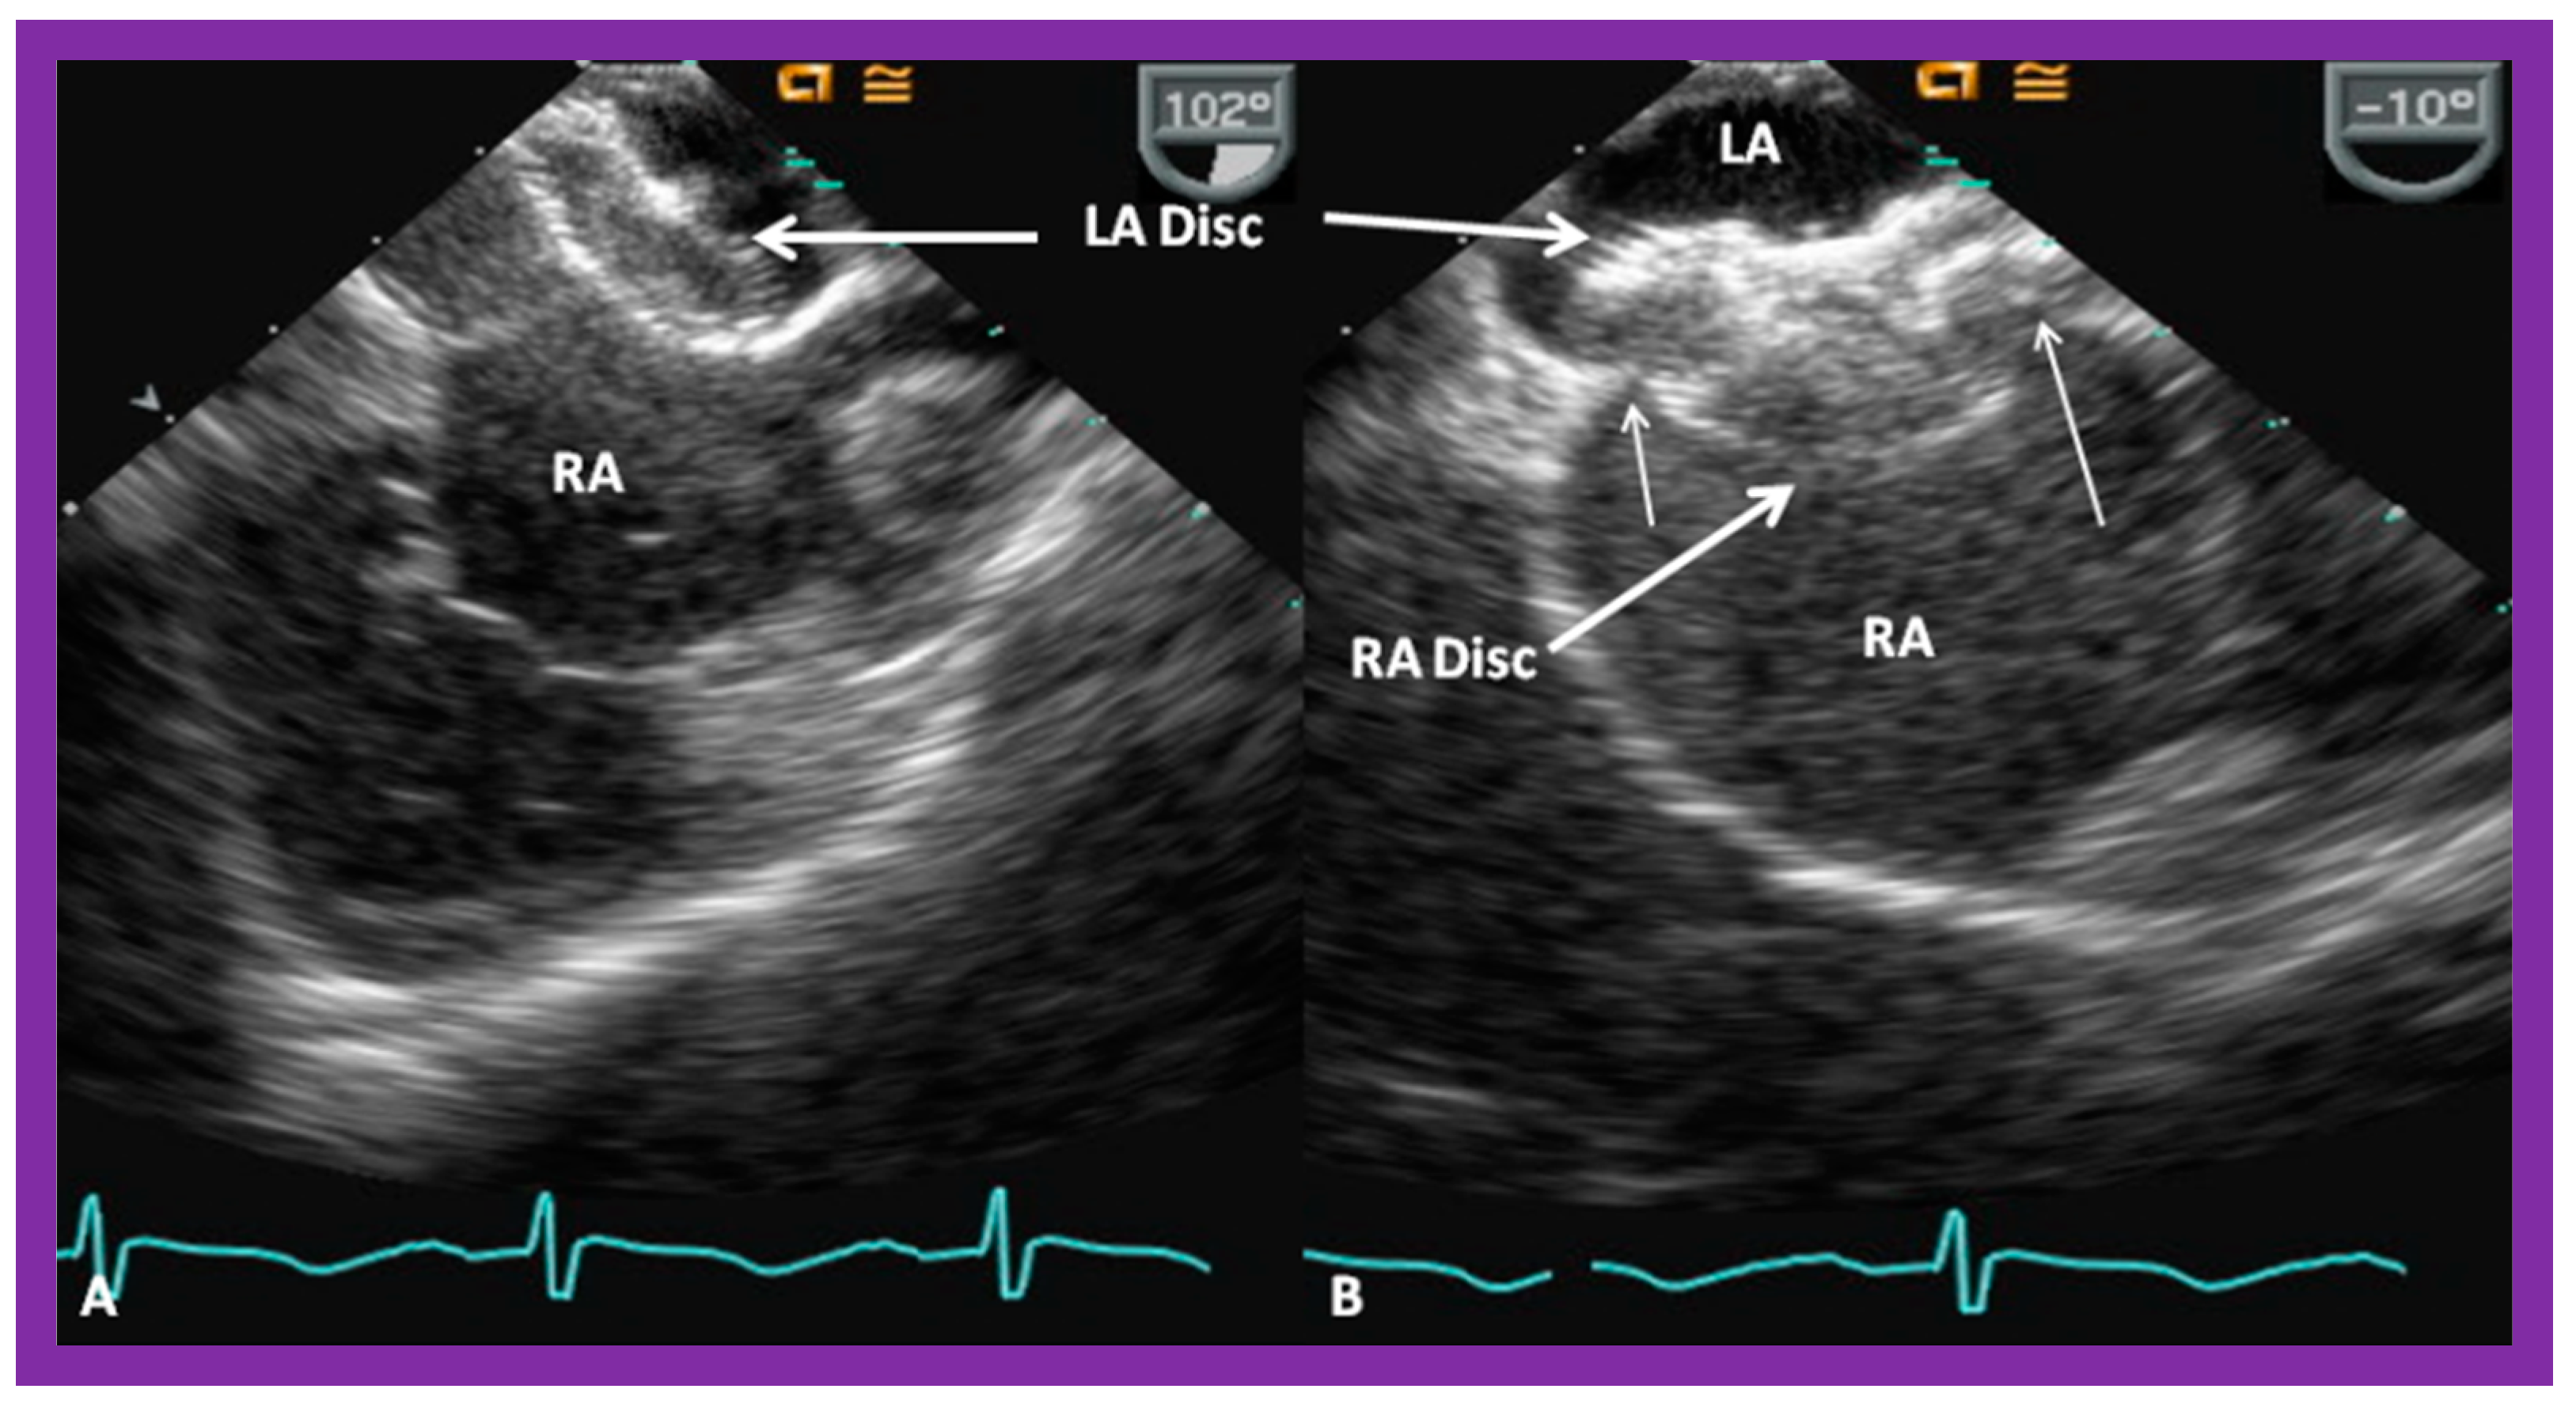

8.1. Amplatzer Septal Occluder

8.2. Gore HELEX® Device

8.5. Septal Rims